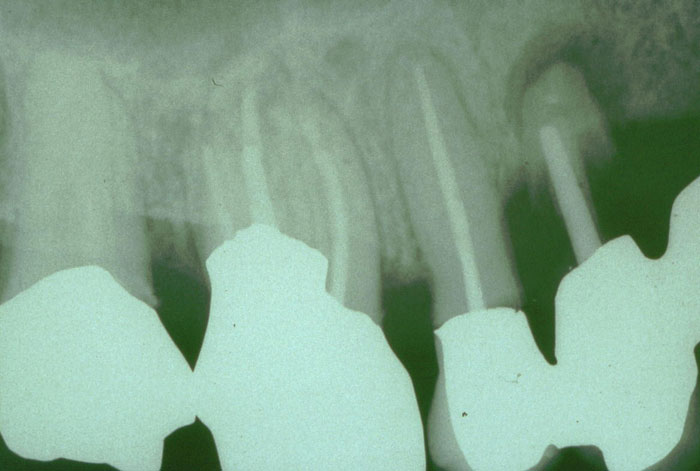

Klinisches Röntgenbild unmittelbar vor Extraktion

Extraktionsgrund: kariöse Zerstörung des Zahnstumpfs bei

ernährungsbedingt generalisierter, florider Karies.